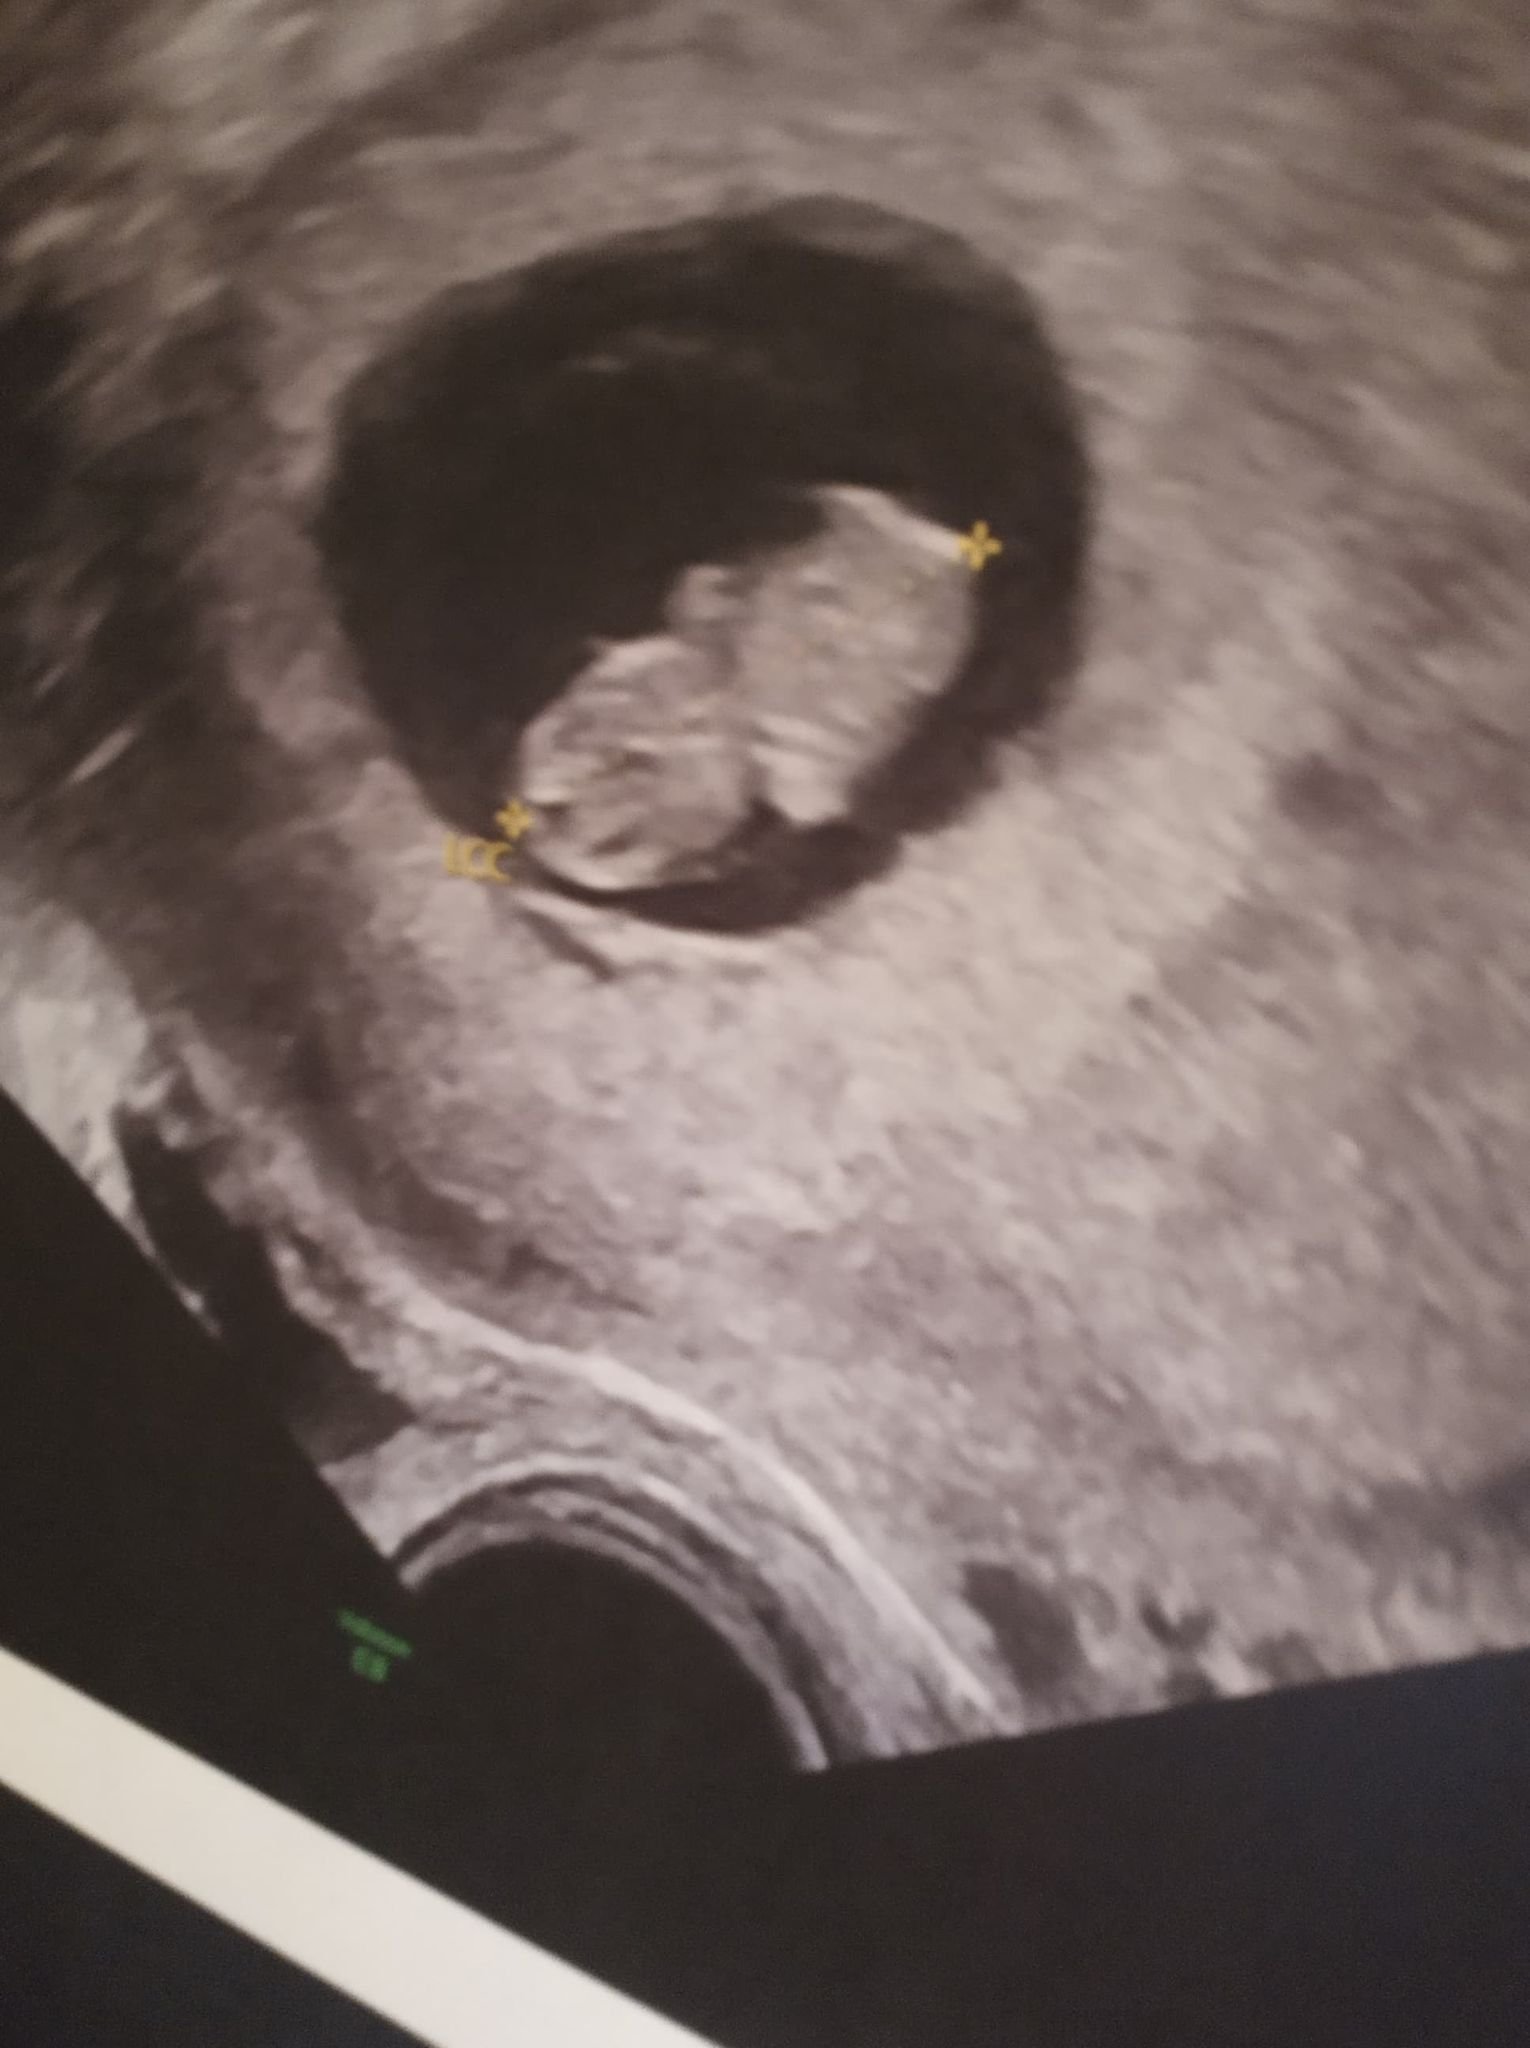

Обичайните симптоми през първите няколко седмици на бременност включват гадене, коремна болка, напрегнати гърди, умора, чувство за тежест и болки в кръста. Важно е да се отбележи, че симптомите могат да варират от жена на жена и всяка бременност е различна. В началото на бременността обичайните симптоми включват гадене, коремна болка, напрегнати гърди, умора, чувство за тежест и болки в кръста. Важно е да се отбележи, че симптомите могат да варират от жена на жена и всяка бременност е различна. При ранна бременност могат да се наблюдават симптоми като кървене или зацапване, които могат да предизвикат безпокойство. Важно е да наблюдавате количеството и цвета на кървенето, тъй като яркочервеното кървене може да е признак на по-сериозен проблем, като извънматочна бременност. Консултация с акушер-гинеколог и извършване на ултразвук са ключови стъпки за оценка на ситуацията. Важно е да запомните, че в много случаи кървенето не е признак на загуба на бременността.